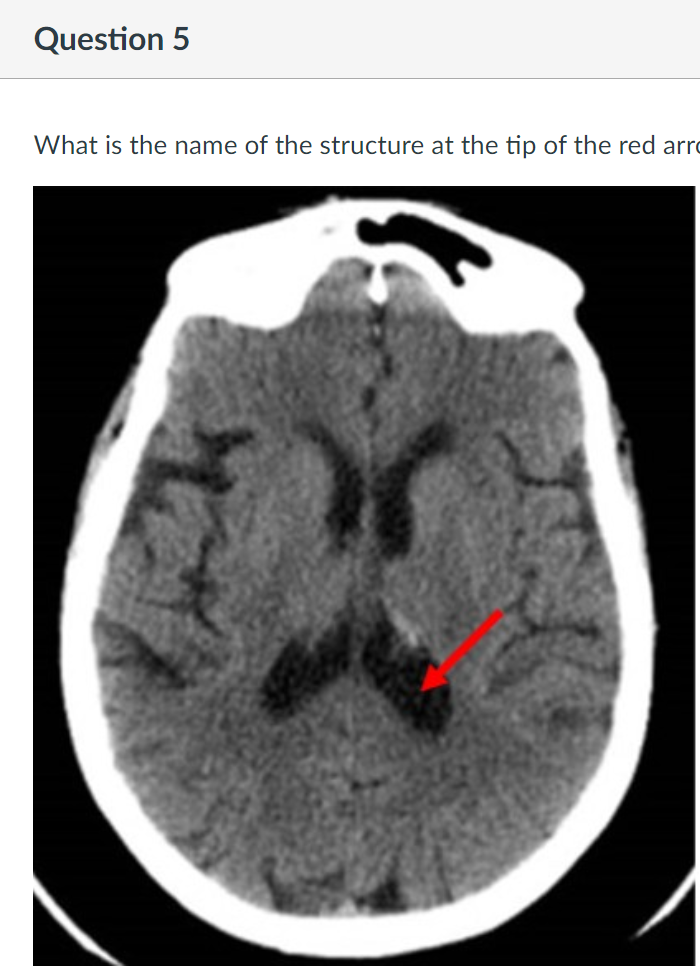

5

Q

A

posterior horn of the lateral ventricle